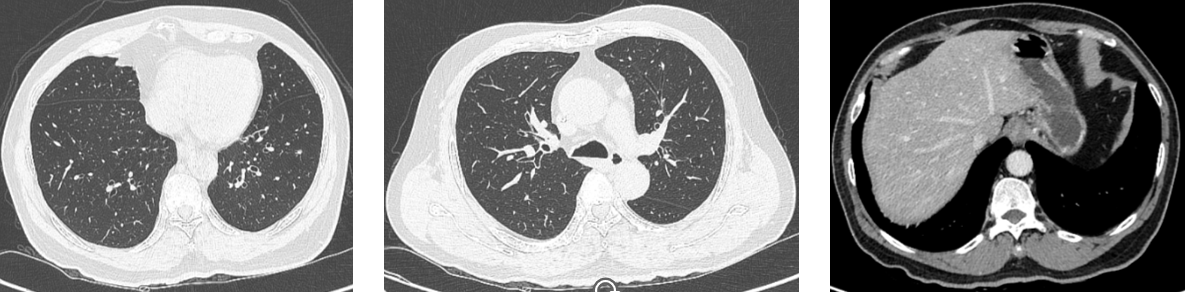

肺部高分辨CT:右肺门软组织结节,考虑转移可能。右肺上、下叶及左肺散在实性、磨玻璃结节。

胸部CT增强扫描:右肺上叶前段小结节灶,随诊。左肺上叶前段、右肺下叶外基底段炎性灶。右肺上叶小钙化灶。主动脉硬化。

胸部CT增强扫描:右肺上叶小结节灶,较前未见明显变化。右肺中叶、下叶新增炎性灶,双肺少许纤维化灶;右肺上叶小钙化灶。

术后复查CT:1、乙状结肠吻合口壁稍增厚;左下腹壁术后改变;上述较前变化不明显,请结合临床及复查。2、脂肪肝;肝右前叶下段小钙化斑;3、双肺纹理清晰,气管支气管通畅,未见狭窄或阻塞征。双肺见散在多个实性小结节影,大者位于右肺中叶内侧段近水平裂处,大小约0.5 cm×0.3 cm(肺窗薄层187),边界清晰。

2021年8月 术后辅助治疗后复查腹部CT:1、双肺多发小结节,部分较前稍增大;2、肝右后叶上段结节,较前新出现。双肺多发实性小结节,稍大者位于左肺下叶前内基底段,大小约0.9 cm×0.5 cm(肺窗薄层281,前片该结节直径约0.5 cm);左肺上叶尖后段厚壁透亮结节,大小约1.1 cm×0.9 cm(肺窗薄层156),粘连邻近肺小血管。

2022年10月 双肺多发实性小结节,较大几个病灶约1.9 cm×1.4 cm(右肺下叶前基底段、肺窗薄层221)、1.6 cm×1.3 cm(左肺上叶尖后段,肺窗薄层157),形态不规则,边缘见分叶及毛刺,病灶内见空泡,增强扫描不均匀强化,部分粘连邻近肺小血管。

肝脏边缘光滑;平扫肝实质密度减低,右前叶下段见点状致密影;肝右前叶上段可见一团片状低密度区,大小约4.2 cm×3.1 cm,增强未见确切强化;肝左外叶、右前叶下段见稍低密度结节影,大者位于左外叶,大小约2.5 cm×2.2 cm。